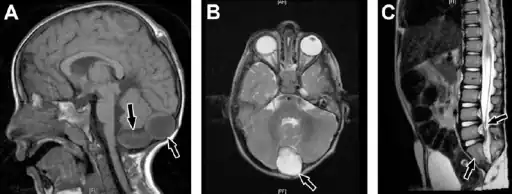

- Caudal regression syndrome-a) Brain MRI shows 2 cystic structures at the region of cisterna magna b) cyst is also shown on axial T2-weighted image c) MRI dorsolumbar spine showing abrupt cutoff and bulbar configuration of conus medullaris at the level of L1